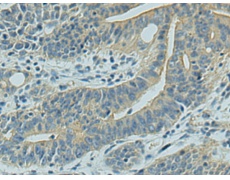

IHC positive control: |

Human gastric cancer and Human tonsil |

IHC Recommend dilution: |

150-300 |